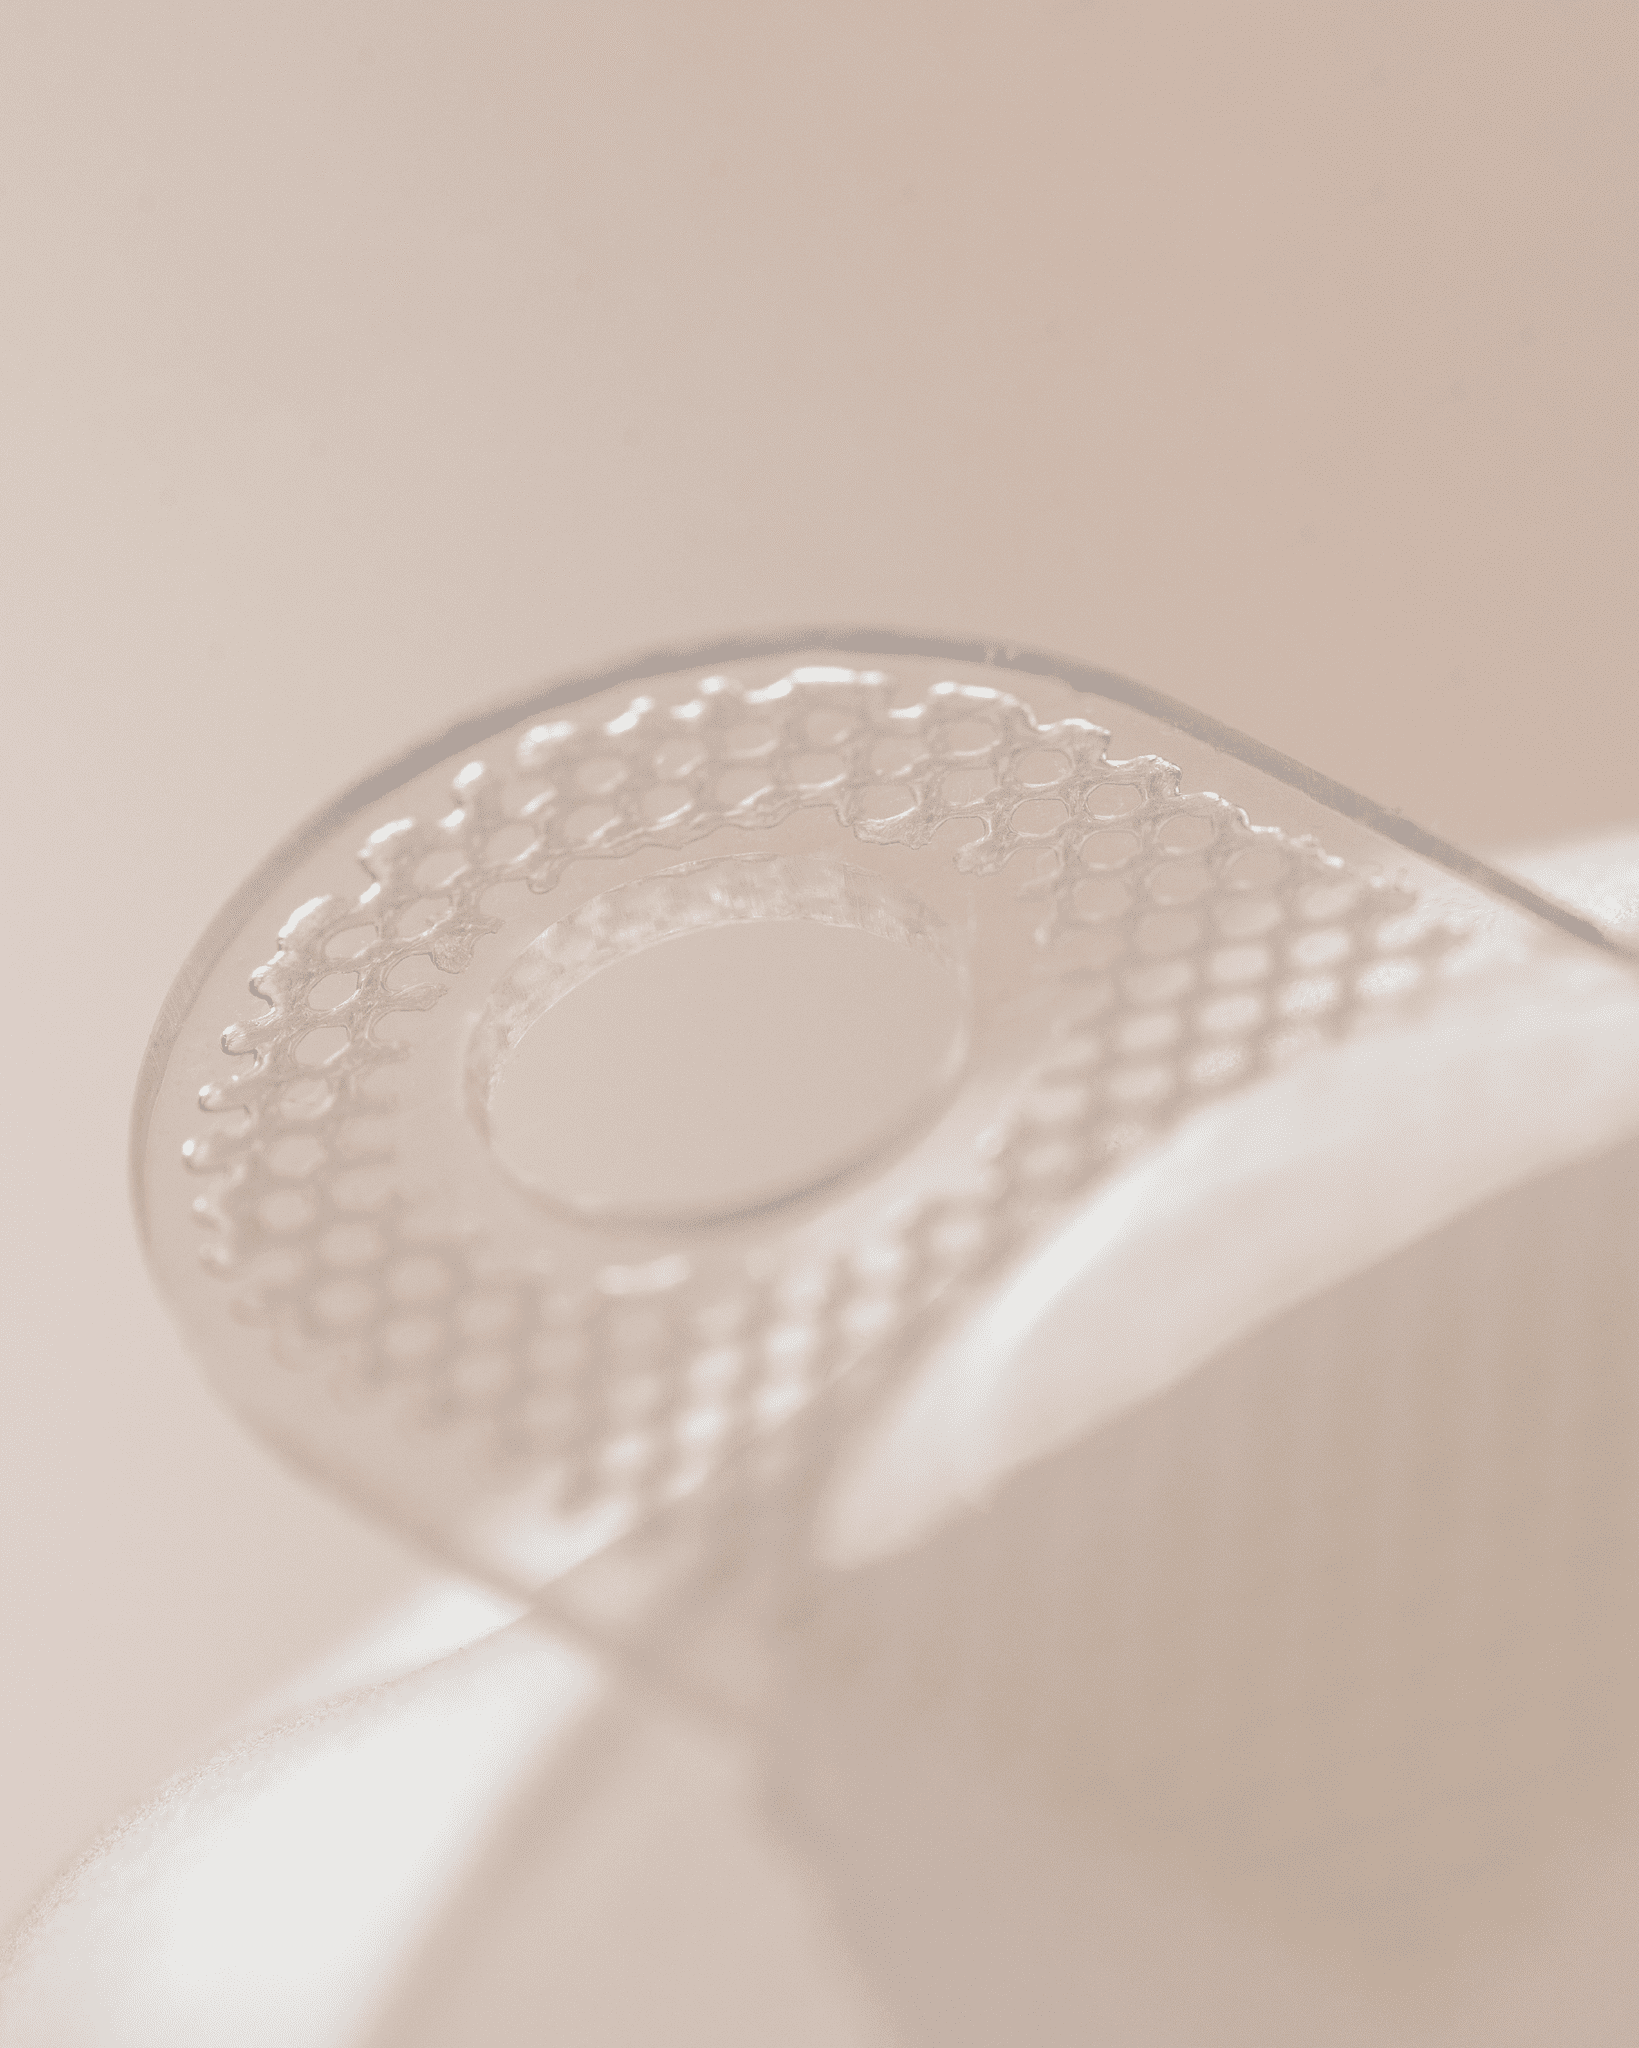

Motiva® Round Plus

Сбалансированная мягкость и упругость с полным и округлым верхним полюсом груди

Motiva Ergonomix®

Разработан для имитации внешнего вида, ощущения и движения натуральной ткани груди

Motiva Ergonomix2®

Разработан для улучшенной эргономики и еще более мягкого импланта, чем у Ergonomix®

Преимущества имлантатов Motiva

Технология Q Inside Safety Technology – микро транспондер хранит в себе информацию об имплантате, которая может быть доступна через специальное считывающее устройство – Reader.